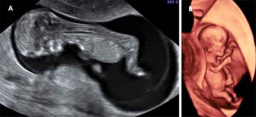

Ecografía de embrión de 9 semanas

El embrión de 9 semanas de gestación mide aproximadamente 22 milímetros. El corazón está prácticamente formado. El embrión tiene una prominente cabeza y esbozos de lo que serán sus brazos y piernas. Ecografía en 2D y 3D de embarazo de 9,4 semanas El embrión mide 24 milímetros. Cada vez...